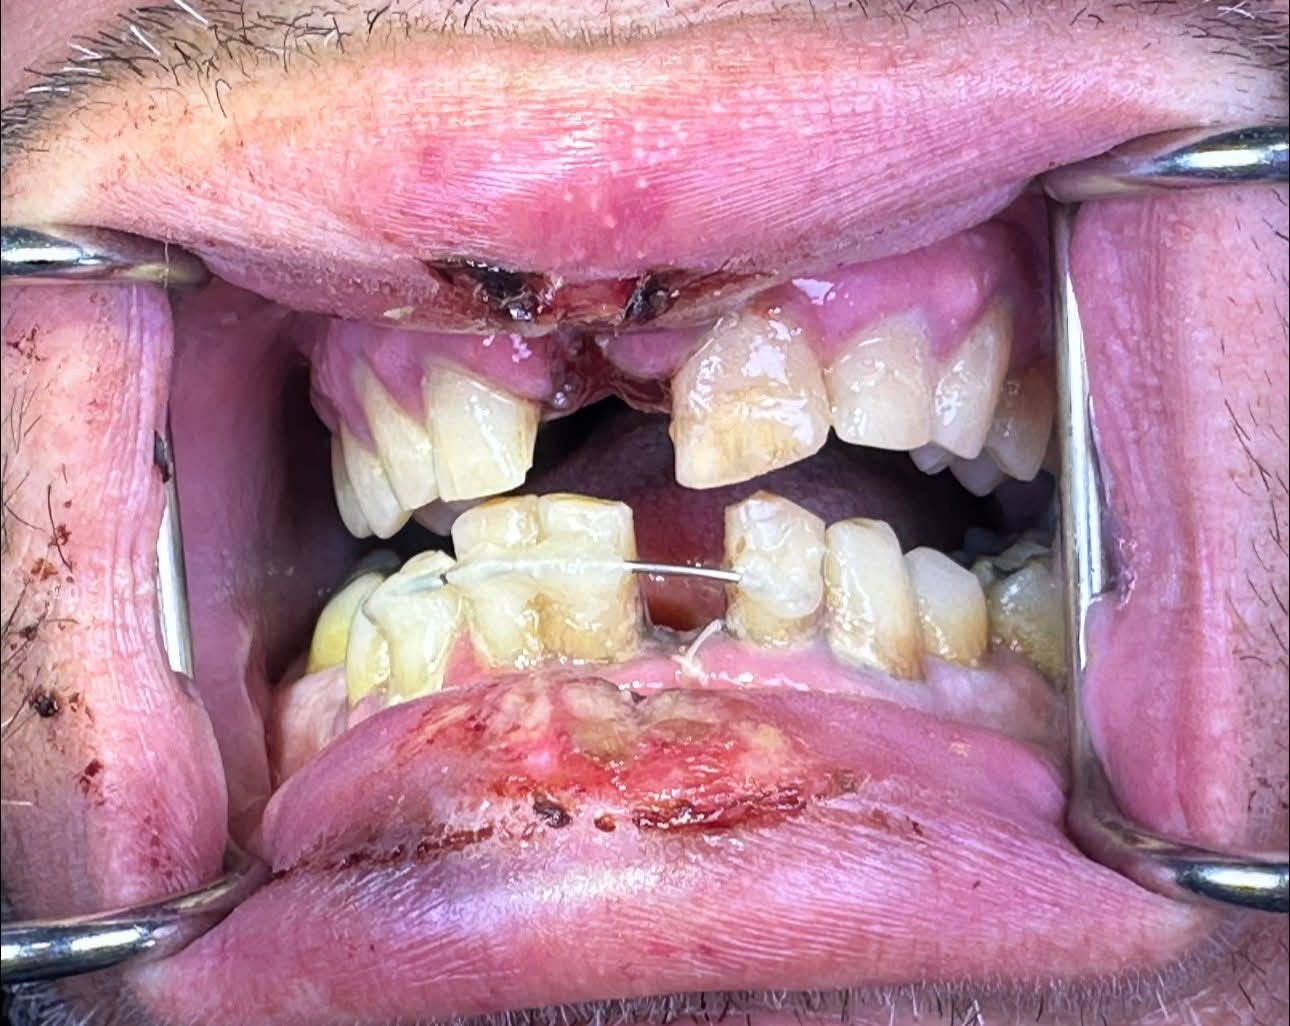

Το αποτέλεσμα το βλέπετε, τα δύο του δόντια εκγομφώθηκαν τα υπόλοιπα πρόσθια άνω και κάτω απέκτησαν κινητικότητα και τραυματίστηκαν τα χείλια του

Ο φίλος μου είχε ένα ατύχημα, έσκασε Ηλεκτρονικό τσιγάρο την στιγμή που το είχε μπροστά στο στόμα του

Όπως μου περιέγραψε αυτό ήταν αποτέλεσμα τις ανάκρουσης του τσιγάρου το μπροστά κομμάτι του τσιγάρου εκτοξεύτηκε στην κουρτίνα όπου άρπαξε φωτιά